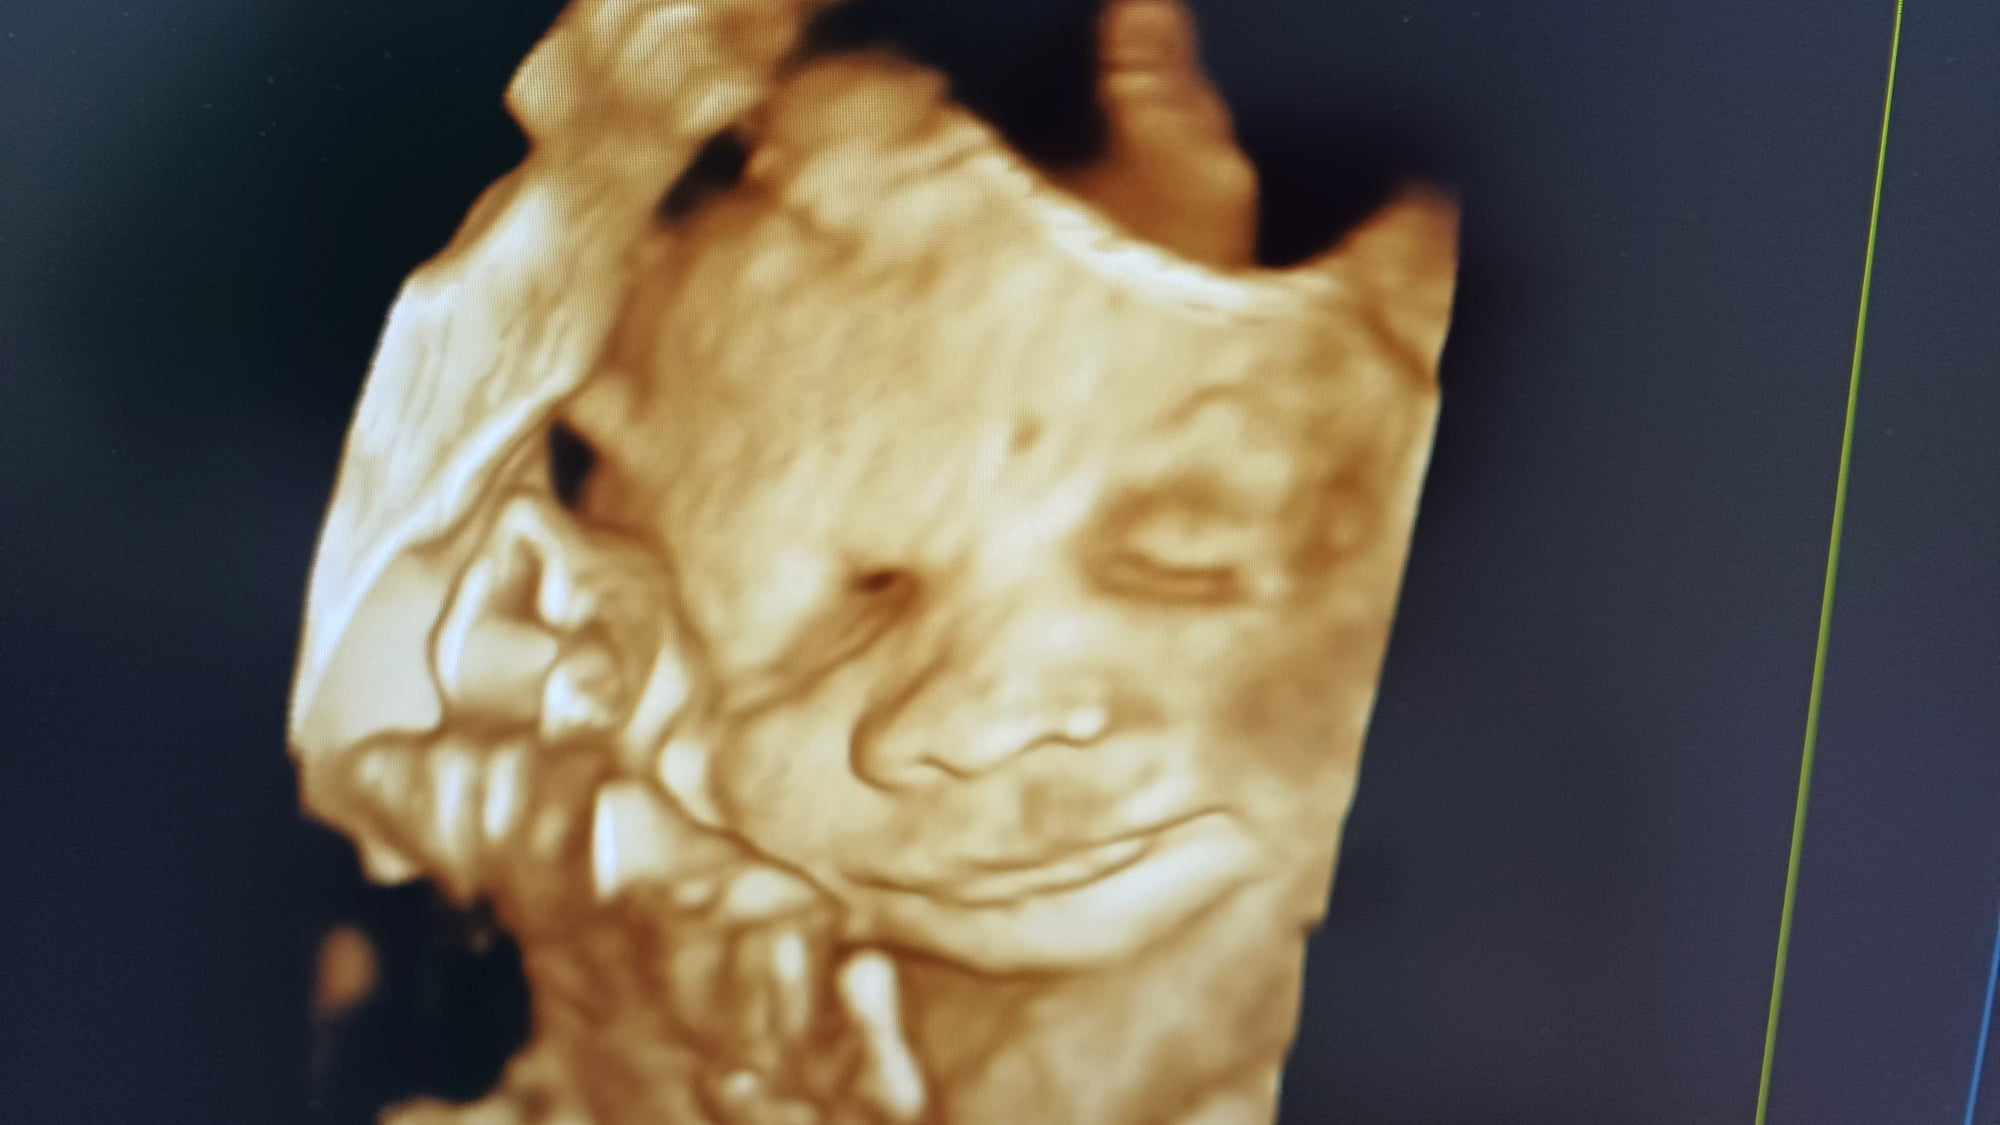

Pozrite si fotky z nášho moderného pracovného prostredia

Naša gynekologická ambulancia je vybavená modernou technikou a poskytuje pacientkom príjemné a komfortné prostredie pre všetky druhy vyšetrení a konzultácií.